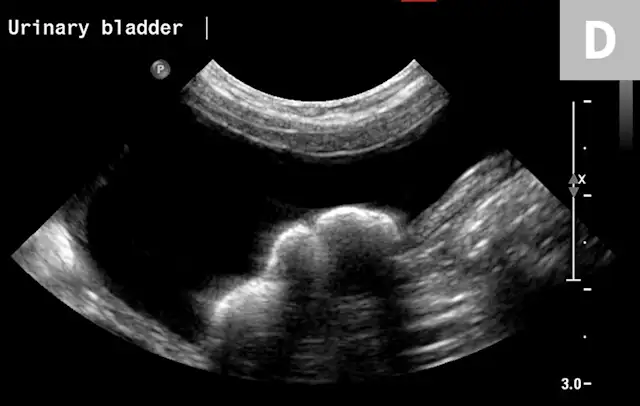

FIGURE 9A

1 / 2

Lateral radiograph of a bulldog presented for recurrent hematuria and stranguria. The study was negative for mineral opaque urinary bladder calculi.

Cystine and urate calculi are less common overall, but more common in bulldog and dalmatian breeds, respectively. These are often non-mineral opaque and are unable to be visualized with survey radiography alone.18 One helpful mnemonic for remembering the non-mineral opaque calculi is “I can’t C U.” Cysteine and urate calculi cannot be visualized as they often do not mineralize. For non-mineral opaque calculi, contrast cystography or ultrasonography will aid in detection (Figure 9).